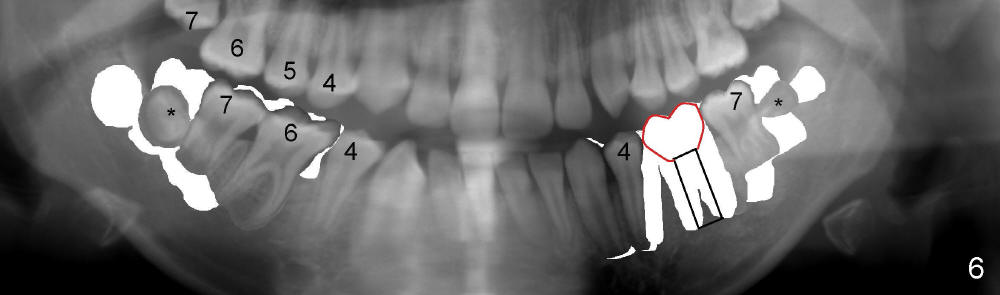

Plan B is shown in Fig.6 when the LL 6 has to be removed due to RCT failure.  The orthodontic movement remains the same except LL6.  The edentulous space will be kept until the patient turns 18 years old.  An implant is placed (black box) and a crown is installed (red outline).